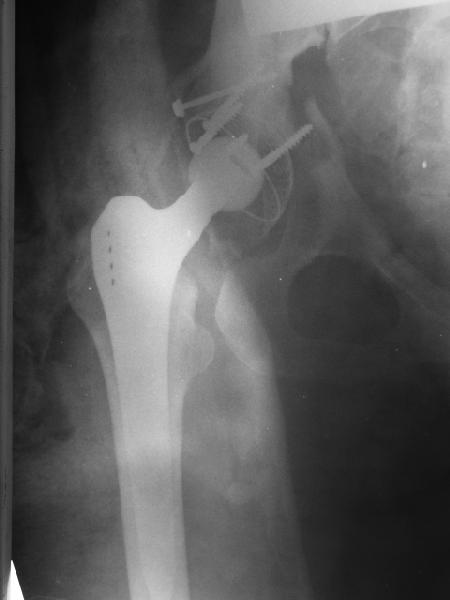

Обратились коллеги из городской больницы N36. Женщине 39 лет по поводу диспластического коксартроза около года назад выполнено эндопротезирование правого тазобедренного сустава. Вчера ехала на госпитализацию на протезирование второго сустава, и попала в аварию.

Получила поперечный перелом правой вертлужной впадины (снимок прилагается) с переломом ветвей лонной кости на другой стороне (inlet view также в приложении), а также поперечный перелом дистального метафиза бедра на этой же стороне. Что посоветуете в отношении протеза и впадины? Спасибо заранее.

A colleague of mine from another hospital requests opinion. A female 39 years old was operated ~1 year ago - right side THA for hypoplastic hip. Yesterday she was going to the hospital for THA of the second hip but got involved in a car accident. She admitted with right acetabular and left rami fractures (images attached). Also trasverse fracture of the right distal femur. Seeking your advice regarding the acetabular fracture. THX!